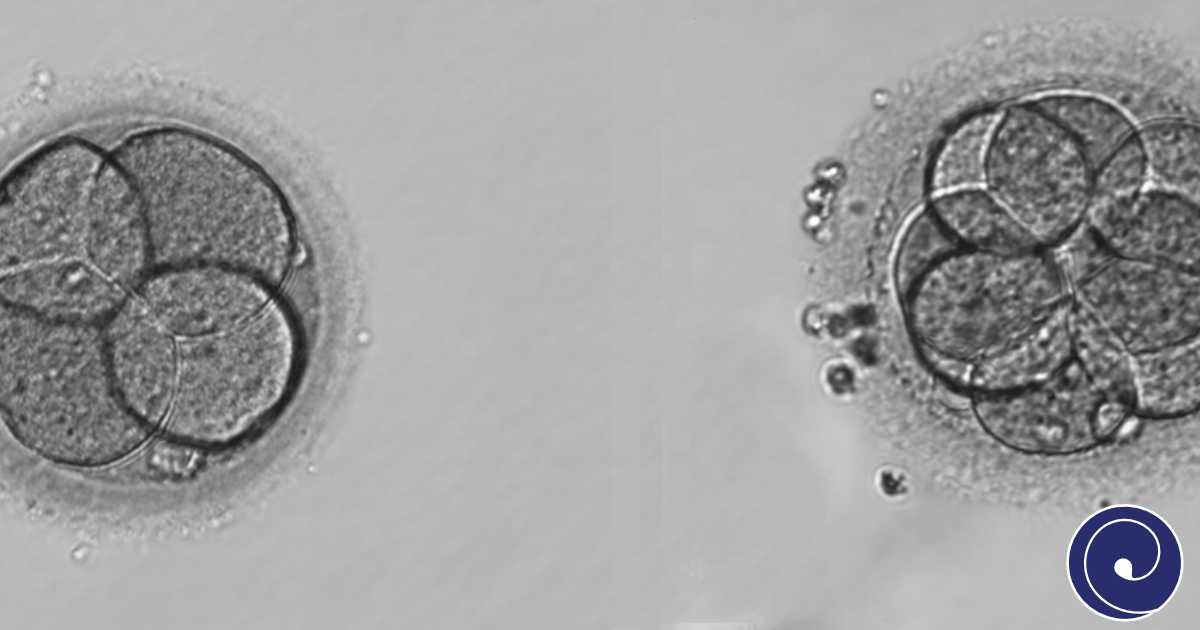

Praćenje razvoja embrija